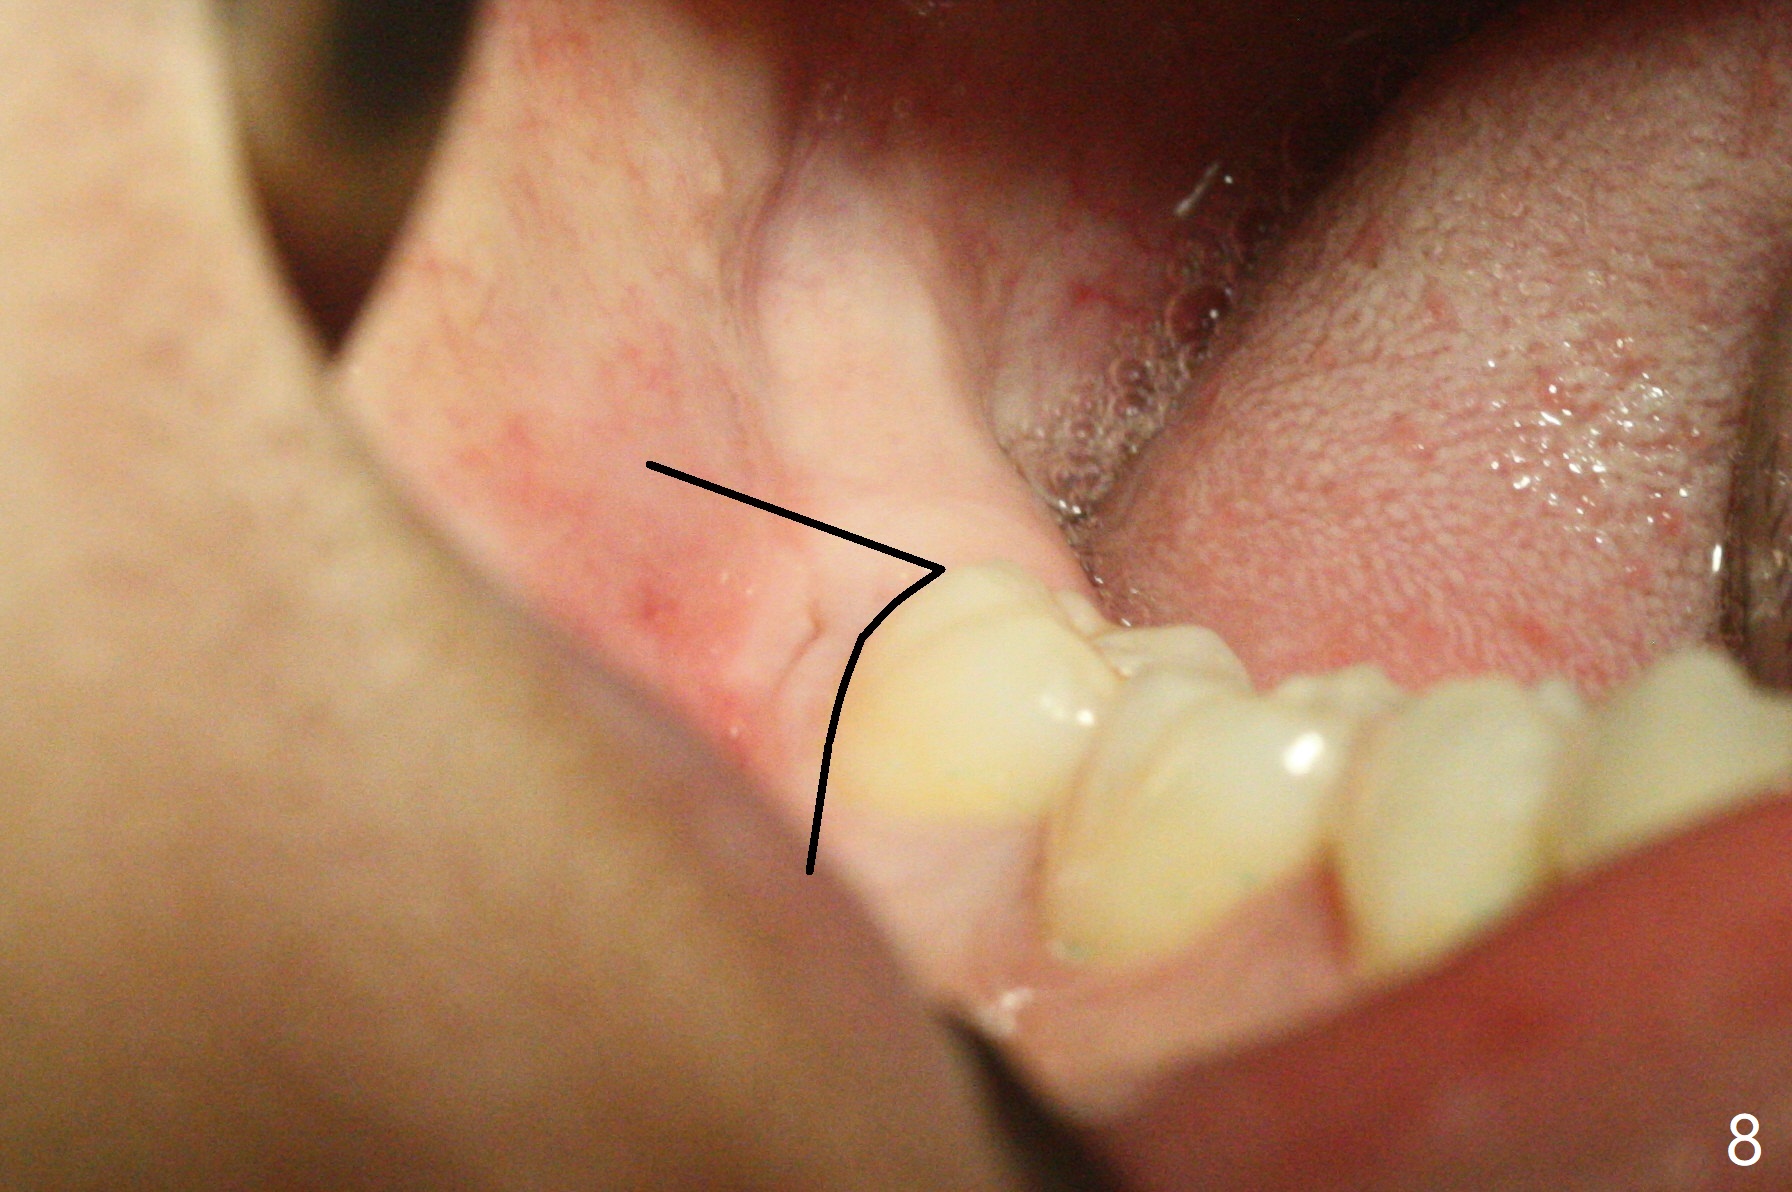

19岁女想在上大学前一次性拔除四个智齿(图一),术前口角涂抗病毒药粉(Acyclovir)凡士林(图二)。图三显示右上磨牙区,L型切口将做在第二磨牙远中(图四),光注射上牙槽后神经止痛还不够,第二磨牙上方还必须使用利多卡因(含肾上腺素1:50,000,而不是1:100,000,止血效果好)。上颌智齿区骨质松软,不必用手机钻头切骨产生purchase point,可以使用Crane Pick插入智齿近中(图五)慢慢撬动牙齿,防止大块上颌结节骨折。如果觉得杠杆作用不够,使用Potts(图六)让牙齿脱位。图七显示右下智齿区,由于舌神经位于牙槽嵴舌侧粘膜下,切口不要超过牙槽嵴(图八)。图九显示术后即刻,下颌智齿牙槽窝密度不同。原来右下牙槽窝放置骨胶原塞,而左下胶原塞。